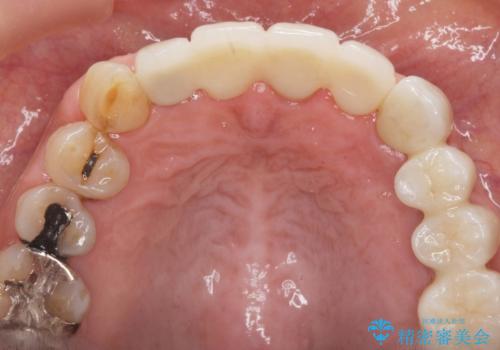

2. ぐらつく前歯 ブリッジ治療の治療中